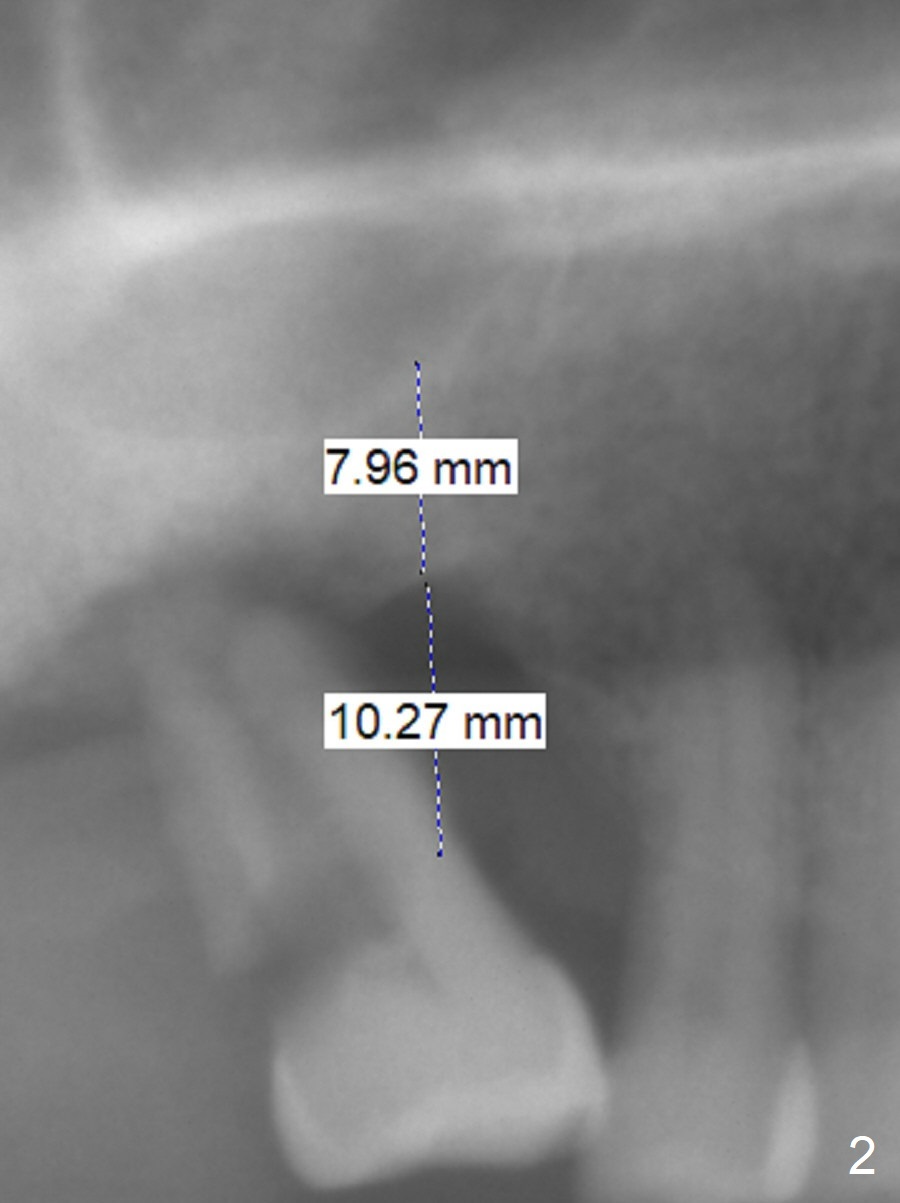

A 53-year-old man has severe peridontitis (Fig.1).  The tooth #3 has exfoliated.  The 1st implant will be placed at #3, where the gingiva seems to be thick (Fig.2: 10 mm).  A mill abutment will be used.